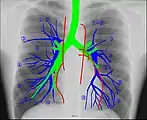

Anatomie radiographique d'une poitrine humaine.